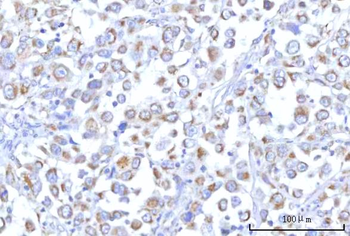

IHC staining of FFPE human lymph node with CD72 antibody (clone BU40). HIER: boil tissue sections in pH9 10mM Tris with 1mM EDTA for 20 min and allow to cool before testing.

IHC staining of FFPE human lymph node with CD72 antibody (clone BU40). HIER: boil tissue sections in pH9 10mM Tris with 1mM EDTA for 20 min and allow to cool before testing.